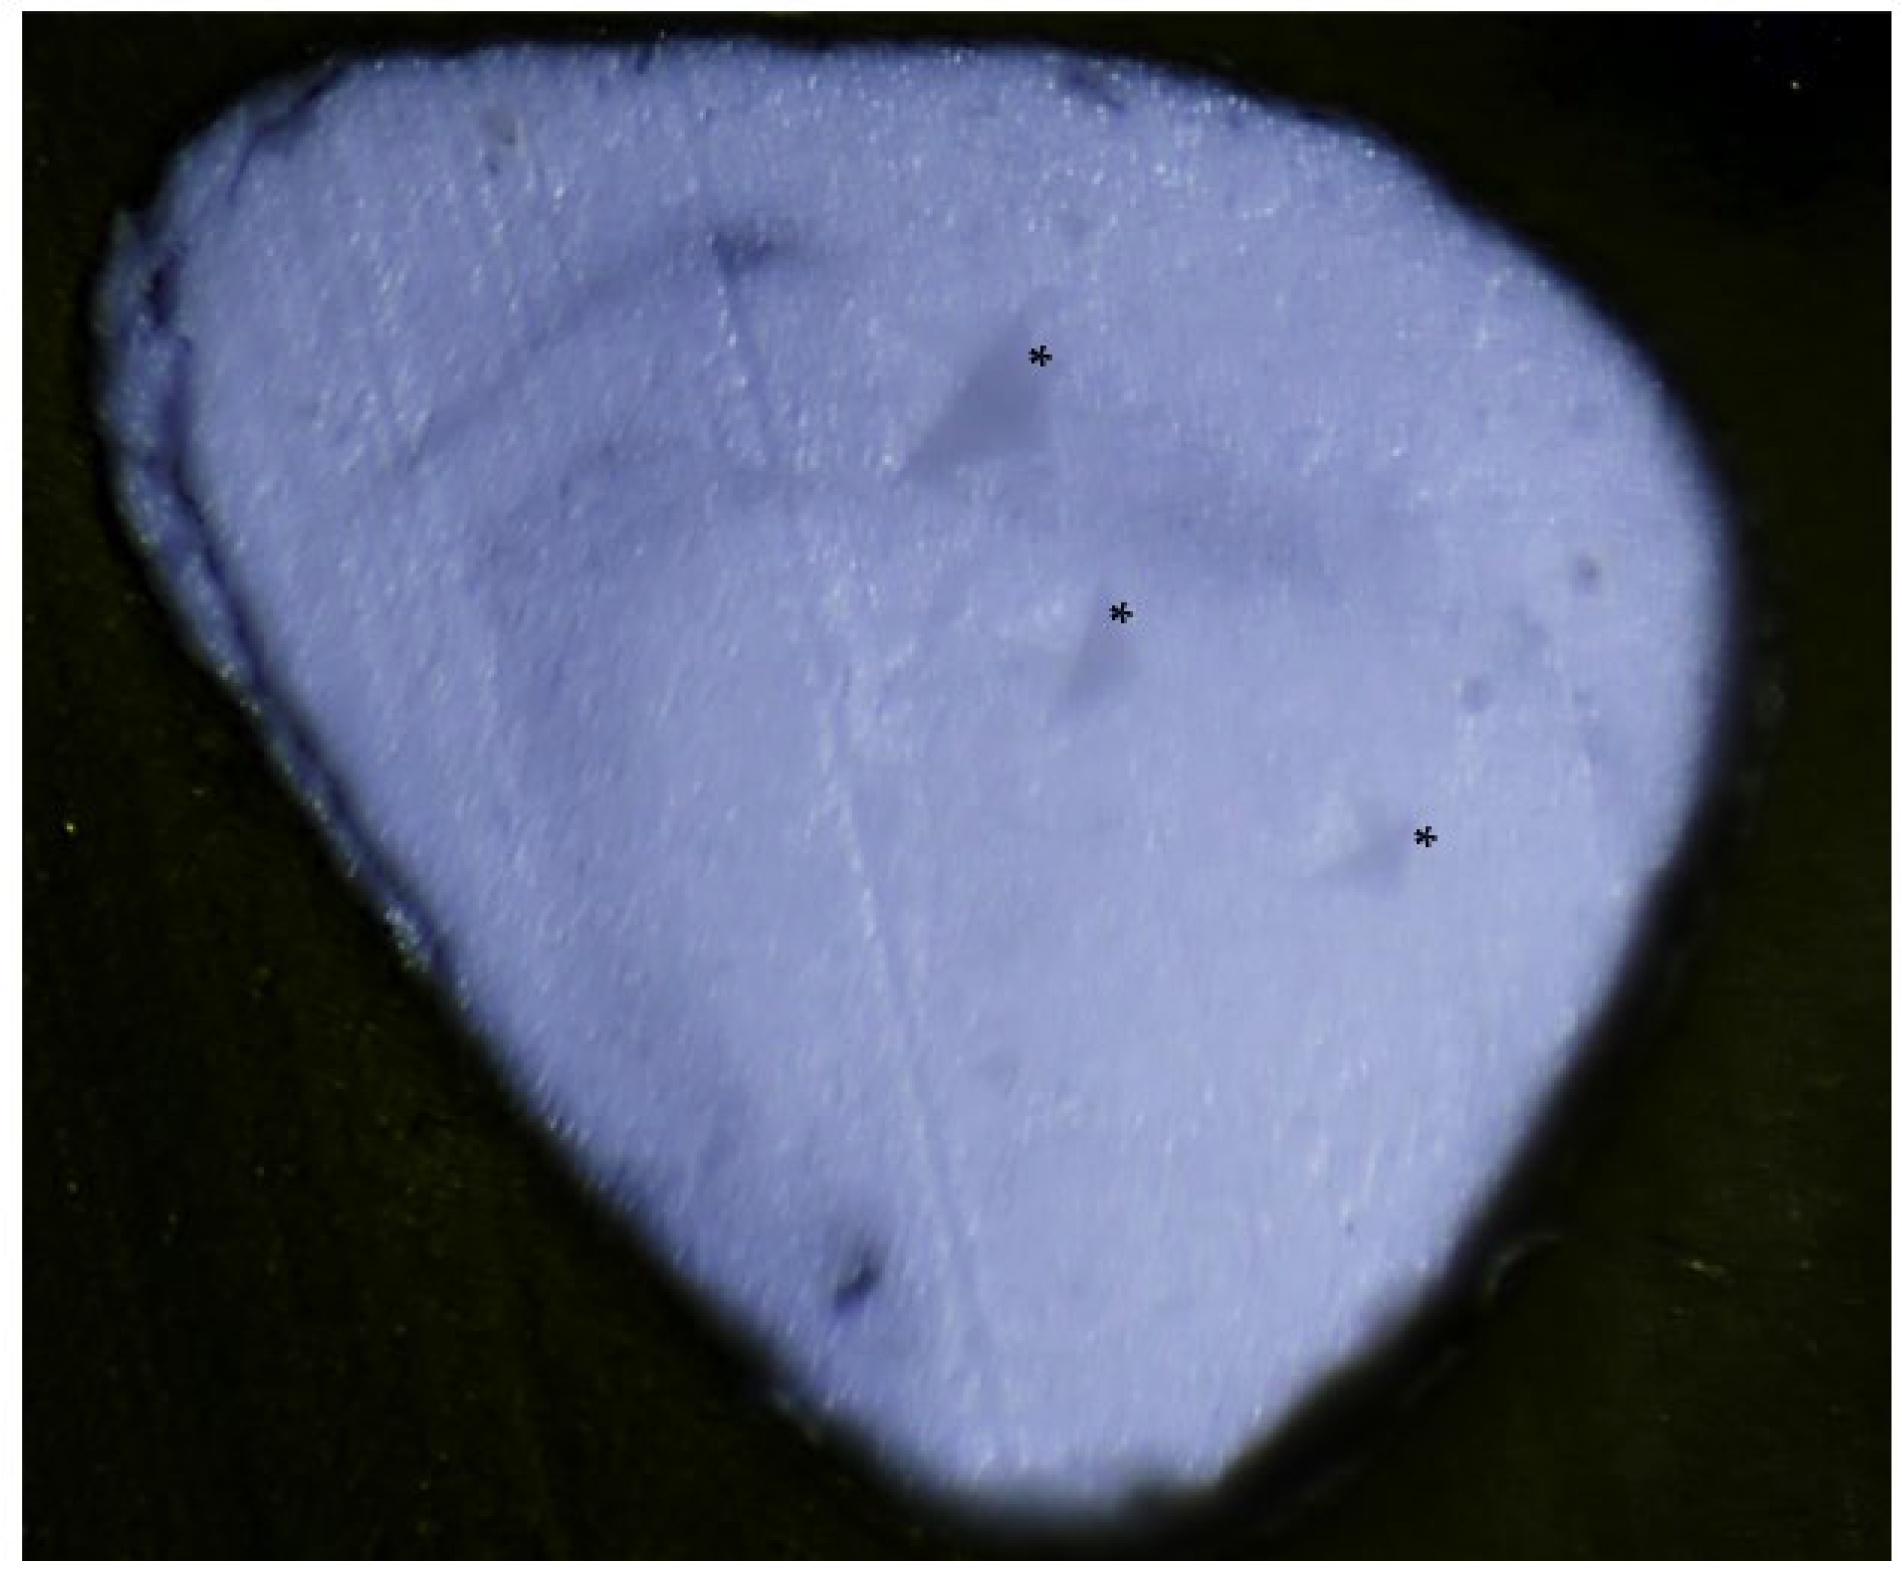

This is the first study to evaluate the effect of ultrasonic condensation during apical plug formation on the microhardness of premixed bioceramic putty Well-Root™ PT. Microhardness is a crucial indicator of a material’s durability and resistance to deformation. The present study found that manual condensation had the highest microhardness values, consistent with previously reported data [

46]. The microhardness values decreased progressively with longer ultrasonic durations, with Group 4 exhibiting the lowest values (

p < 0.05). Microscopic examination of the indented surfaces (

Figure 1) showed no visible cracking or deformation, supporting the suitability of this load for Well-Root™ PT. However, lower loads (100–500 g) are recommended for some brittle biomaterials to minimize the risk of microcracking [

35], and future studies could validate our findings using a range of loads to ensure measurement reliability. To assess the material’s response to loading and unloading, indentation surfaces were examined microscopically post-testing to evaluate surface integrity and deformation characteristics.

The loading and unloading behavior of Well-Root™ PT, as inferred from indentation surface analysis, indicates that brief ultrasonic activation (3 s) and manual condensation preserve surface integrity, as evidenced by sharper indentation edges and higher microhardness values. Prolonged ultrasonic activation (15 s) likely increases surface porosity, reducing resistance to deformation and contributing to lower microhardness (p < 0.05). These findings underscore the importance of optimizing condensation techniques to maintain surface mechanical properties, which are critical for resisting functional stresses and ensuring a durable apical seal.